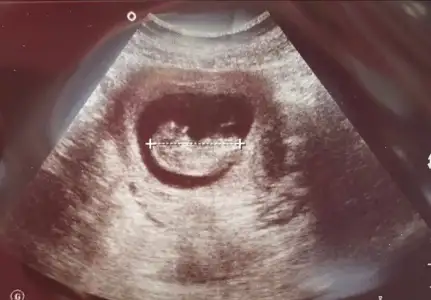

Kız görünüyor11+2 bı tahminde bulunur musun canım Eki Görüntüle 2894305

Kız gibi sanki

Yaa inşallah canım bu usg ablaminki ve 2 oğlu var doktor da demiş umitlenme ama kız gibiKız görünüyor![]()

Kaç haftalık USG 11 12 13 haftalar olmalı nub görünmüyor başka USG varsa